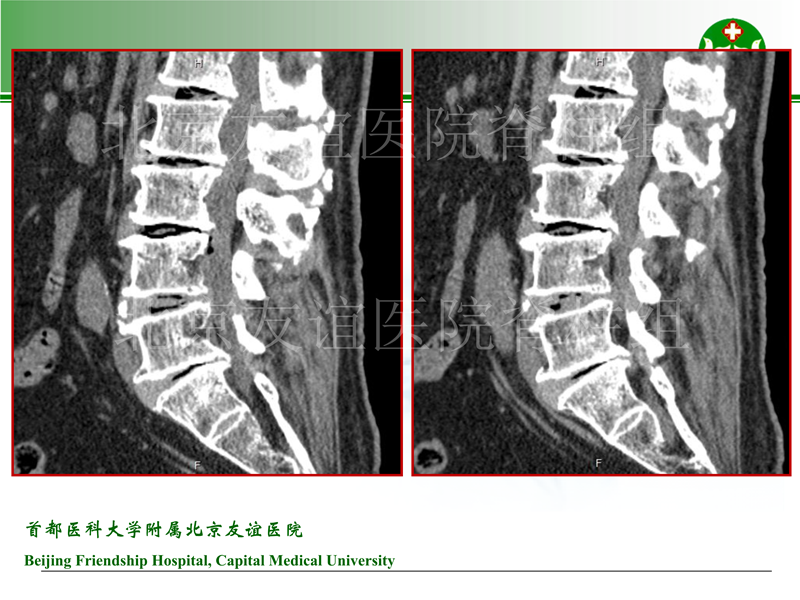

影像片: